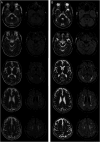

Results: MRI of the brain demonstrated mild diffuse white matter hyperintensities bilaterally. Analysis of optical genome mapping data revealed a 275.54-kb tandem duplication at 5q23.2 [NC_000005.10:g.126637655_126913191dup] comprising 4 genes including the LMNB1 gene.